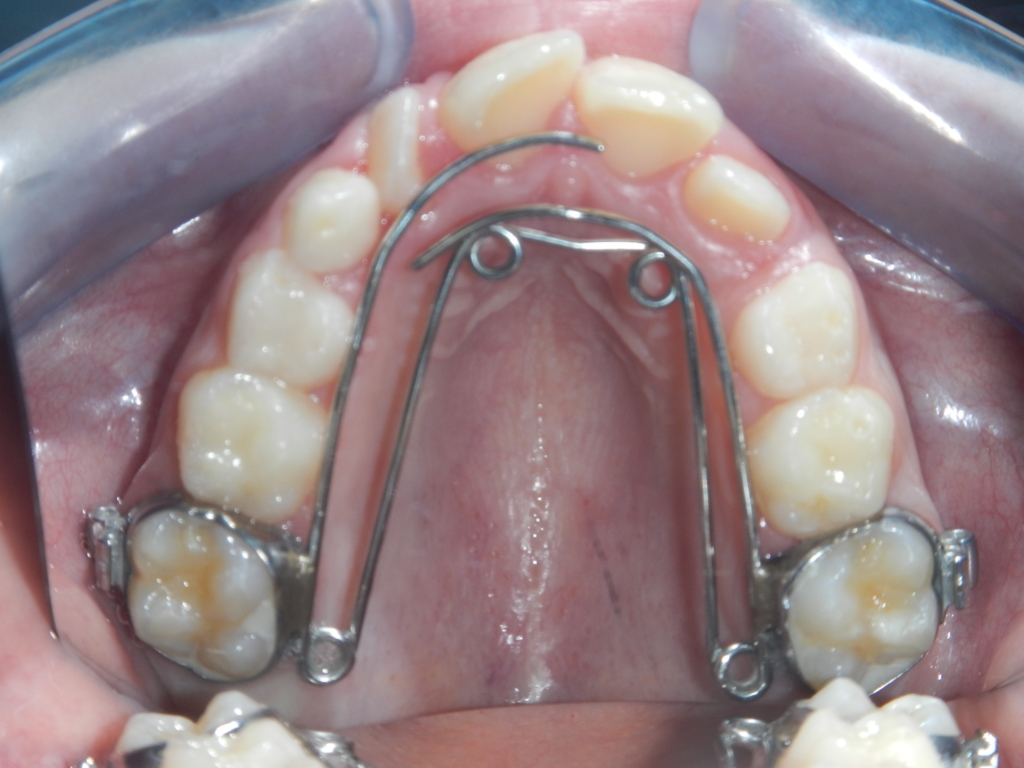

LE QUADHÉLIX

Il permet de corriger un articulé inversé uni- ou bilatérale (c’est-à-dire quand les dents du haut se trouvent à l’intérieur de celles du bas).

Il est porté pendant 6 mois en denture mixte.